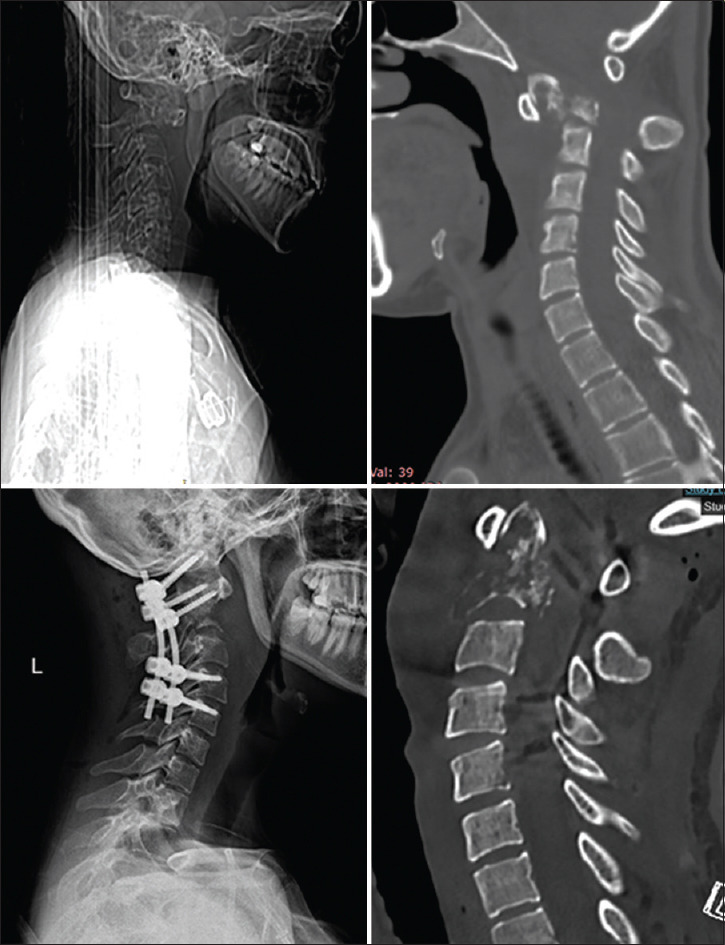

枕颈交界处(OCJ)是一个复杂的解剖区域,对保护下脑干、上脊髓和下颅神经至关重要。该区域的不稳定性可导致慢性疼痛、神经功能缺损或死亡等严重后果。目前已开发出多种用于稳定 OCJ 的手术技术,尤其是使用枕骨髁螺钉,这些技术在提供稳定性和保持颈部旋转方面已显示出良好的前景。本文介绍了两例因C2椎体转移性受累而导致的OCJ不稳定病例,这两例病例均采用枕骨髁螺钉固定术成功治愈。第一例患者是一名 22 岁的女性,患有尤文肉瘤转移;第二例患者是一名 62 岁的男性,患有多发性骨髓瘤。两名患者术后的神经功能和颈椎稳定性均有明显改善,并可观察到穴位重塑。我们的研究结果表明,枕骨髁螺钉固定术不仅可行,而且能有效治疗转移性疾病导致的 OCJ 不稳定。详细的术前评估和使用先进的术中成像技术(如 O 型臂和神经导航)对于最大限度地提高安全性和确保最佳治疗效果至关重要。这项研究强调了枕骨髁螺钉固定术作为一种主要手术方法在适当病例中稳定 OCJ 的潜力。

The occipitocervical junction (OCJ) is a complex anatomical region crucial for protecting the lower brain stem, upper spinal cord, and lower cranial nerves. Instability in this area can lead to severe outcomes such as chronic pain, neurological deficits, or death. Various surgical techniques have been developed for OCJ stabilization, particularly using occipital condyle screws, which have shown promise in providing stability and preserving neck rotation. This article presents two cases of OCJ instability caused by metastatic involvement of the C2 vertebra, managed successfully with occipital condyle screw fixation. The first case involved a 22-year-old female with Ewing sarcoma metastasis, and the second case involved a 62-year-old male with multiple myeloma. Both patients exhibited significant improvements in neurological function and cervical stability postoperatively, with observable den remodeling. Our findings suggest that occipital condyle screw fixation is not only feasible but also effective in managing OCJ instability due to metastatic disease. Detailed preoperative evaluation and the use of advanced intraoperative imaging technologies, such as the O-arm and neuronavigation, are essential for maximizing safety and ensuring optimal outcomes. This study underscores the potential of occipital condyle screw fixation as a primary surgical method for stabilizing the OCJ in appropriate cases.